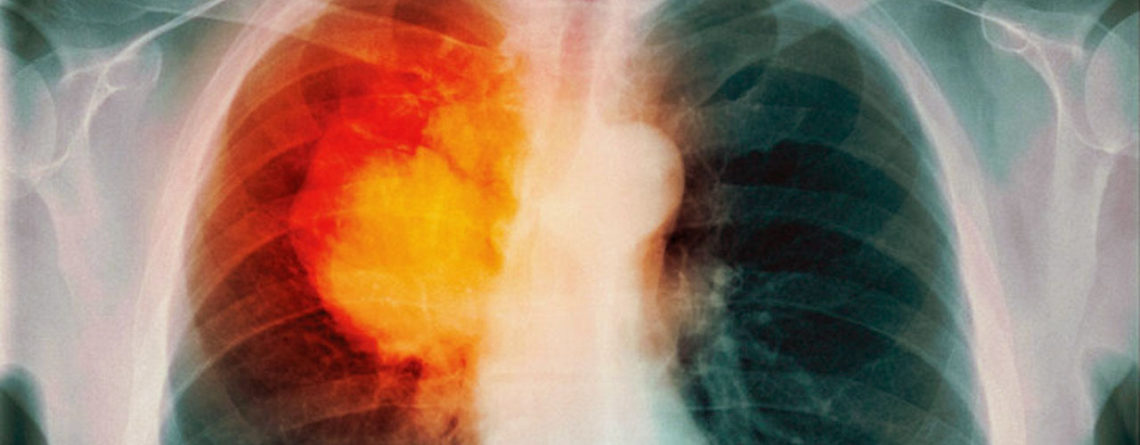

Химиотерапия – тяжелое, но эффективное средство лечения онкологической патологии. Многих пациентов беспокоят осложнения после химиотерапии при раке легкого, и неудивительно: во время курса лечения пациенты могут ощущать слабость, головную боль, их беспокоят общие и частные симптомы.

Медикаментозное лечение направлено на угнетение процессов деления раковых клеток. Как правило, клетки злокачественных опухолей отличаются интенсивным ростом, быстрым делением и распространением по организму.

Метастазы – новые очаги злокачественного процесса, обеспечивают более интенсивное распространение раковых клеток по организму. В раковых клетках происходят особые процессы: их физиология и биология отличается от здоровых клеток, что обеспечивает им значительный рост и деление за короткий промежуток времени.

Во время химиотерапии происходит торможение роста злокачественных очагов. Пациенты с раком легких после химиотерапии отмечают облегчение в «онкологическом плане», то есть, их перестают беспокоить симптомы рака легких, но могут появляться побочные эффекты проведенного лечения.